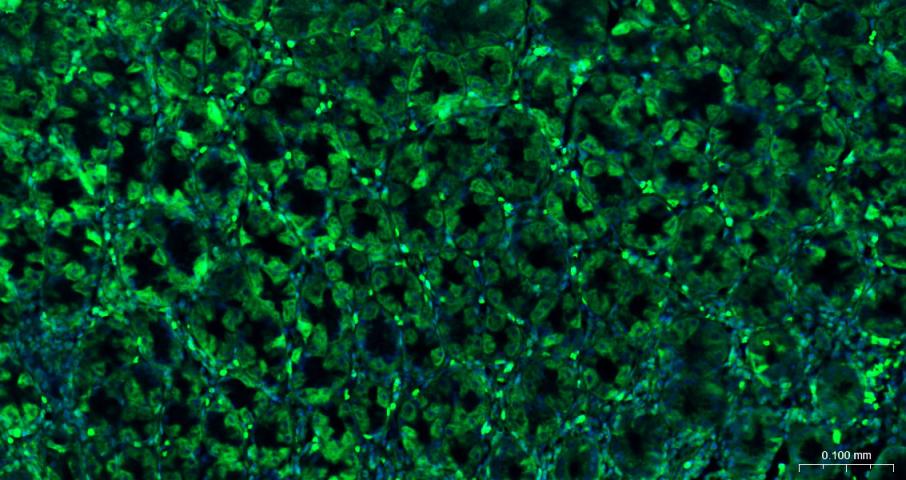

Paraformaldehyde-fixed, paraffin embedded Human Breast Cancer; Antigen retrieval by boiling in sodium citrate buffer (pH6.0) for 15 min; Antibody incubation with eIF4E Monoclonal Antibody, Unconjugated (bsm-63259R) at 1:200 overnight at 4°C. Followed by conjugated Goat Anti-Rabbit IgG antibody (green, bs-0295G-BF488), DAPI (blue, C02-04002) was used to stain the cell nuclei.